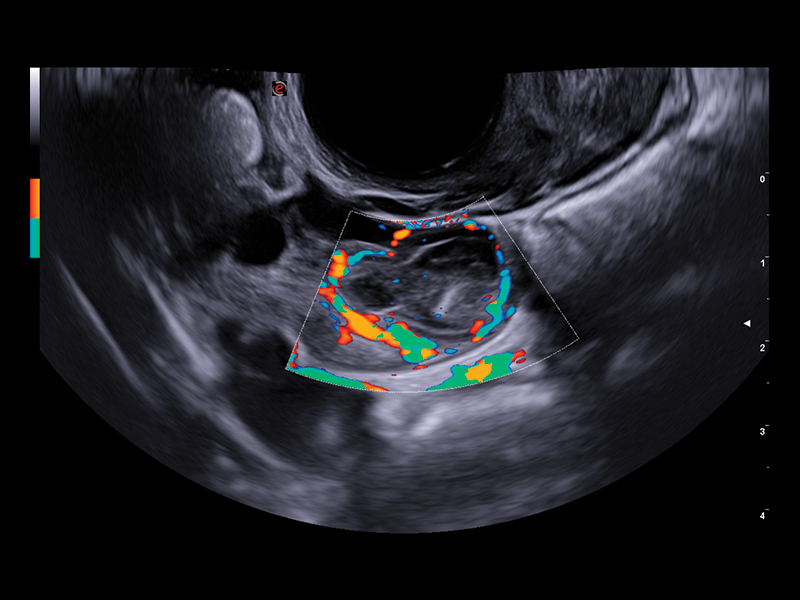

The improved vascular image quality together with the extreme sensitivity of Esaote Doppler technologies (Power Doppler and microV) allow the detection of tiny vessels, to precisely assess the extent of the vascularization, to provide you with a better understanding of certain pelvic abnormalities such as fibroids, polyps, or endometriosis conditions.